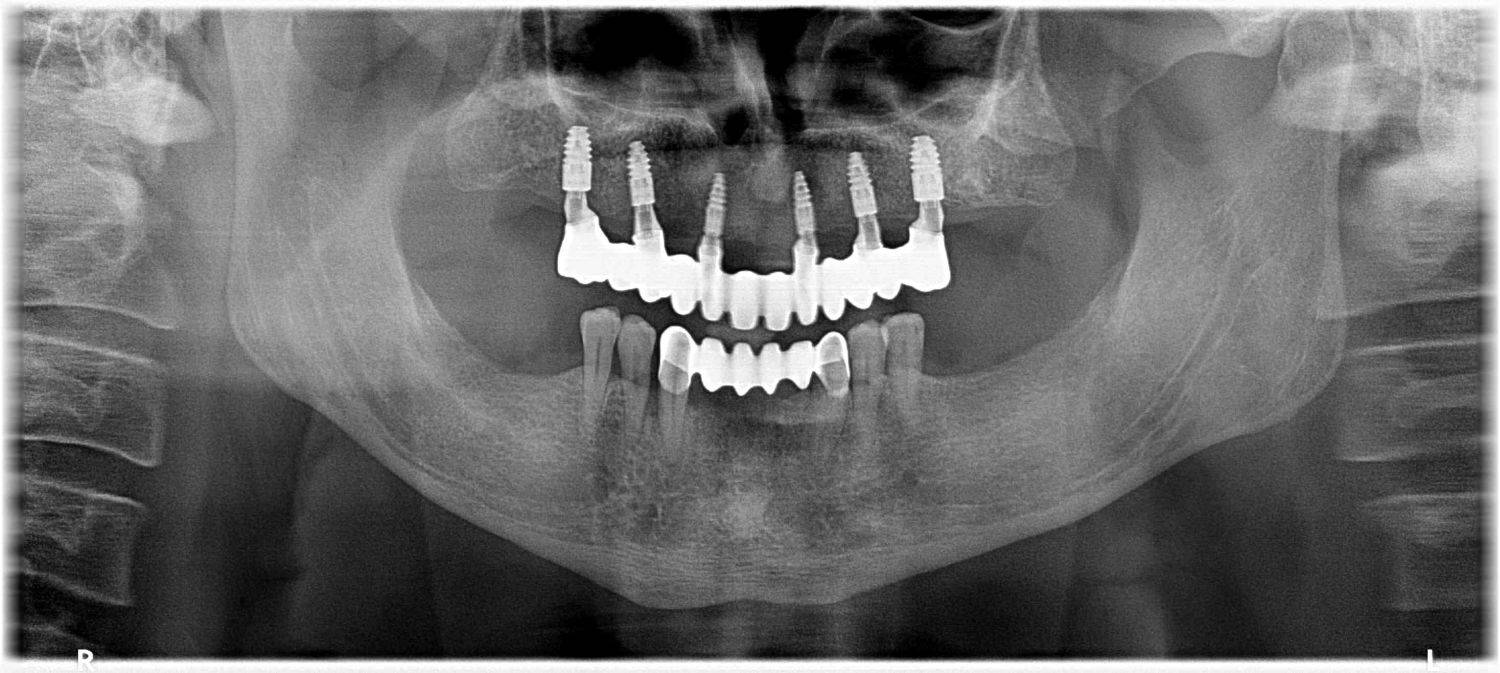

1. eset

A páciens fogágybetegség miatt érkezett hozzánk. A felső fogak menthetetlen állapotban voltak. All on 6 megoldásként a felső fogak eltávolításakor 6 implantátum került beültetésre és a páciens azonnal egy fix ideiglenes hidat kapott. 4 hónapos gyógyulási idő után készült el a felső fémkerámia leplezésű körhíd.